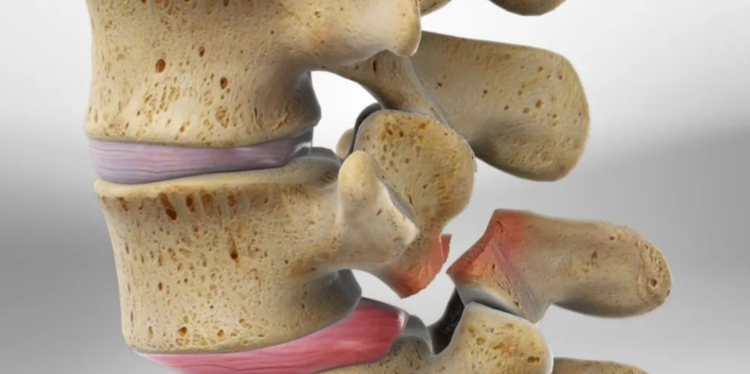

腰椎滑脱该怎么诊治?看这篇就够了!

腰椎滑脱是一种比较常见的疾病,是指其中一节段椎体与下方椎体向前滑动或脱离。